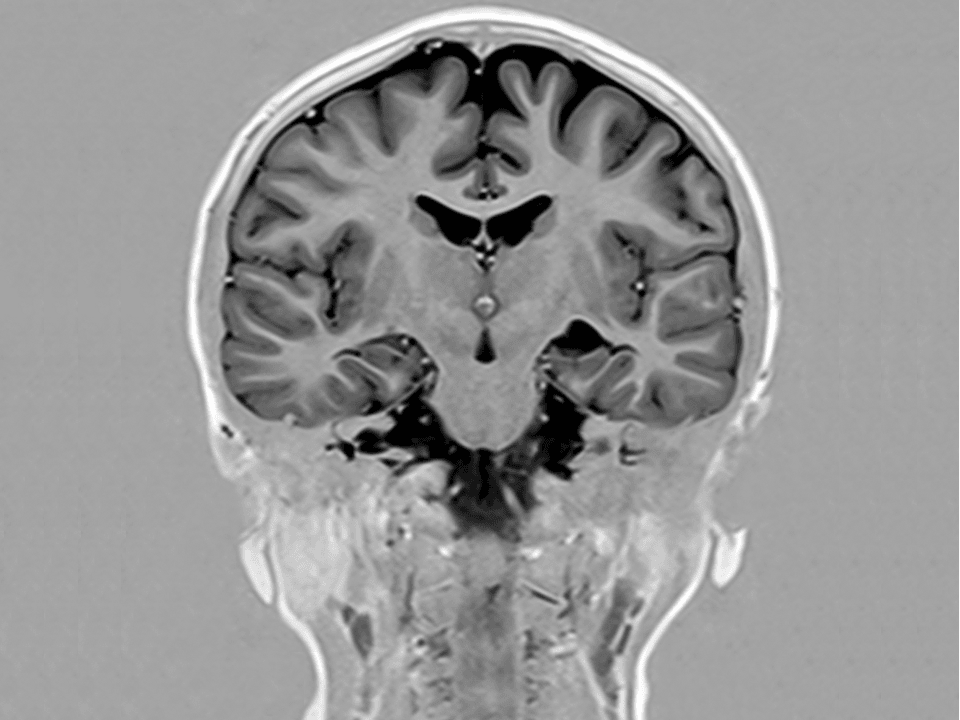

Excellent performance and pristine image quality for standard and adv. applications like functional imaging(BOLD),prefusion or diffusion tensor imaging and tractography.